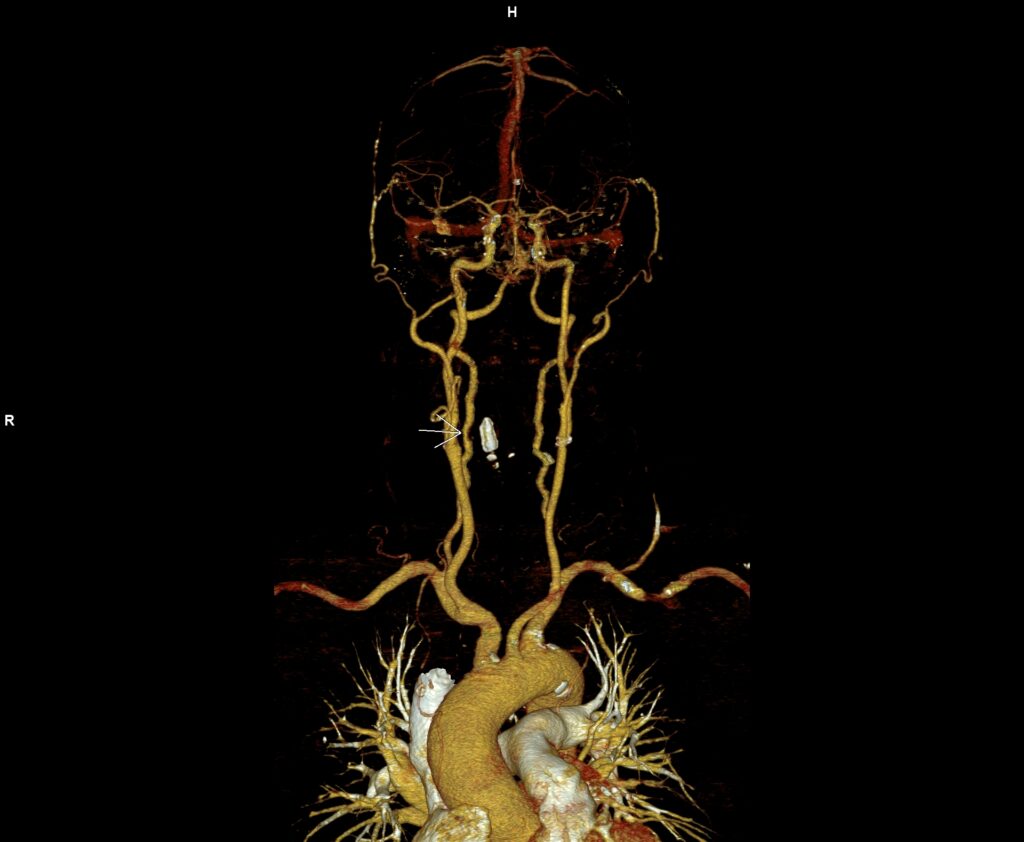

Figura 3: reconstrucție volumică VRT din achiziție angioCT trunchiuri supraaortice

Discuţie caz nr 116: Pe imaginile prezentate se observă reducere de calibru de 60-70% a arterei vertebrale drepte datorată compresiei extrinseci de către o hernie de disc extraforaminală. Leziunile severe de artere vertebrale, mai ales la pacienții tineri care nu au dezvoltat colaterale, produc leziuni cerebrale de fosă posterioare și / sau ganglioni bazali. La acești pacienți se recomandă angioCT sau, unde este posibil și există expertiză, angioRM de trunchiuri supraaortice pentru suspiciune de disecție de perete vascular.

DE LUAT ACASĂ!!! În cazul unei suspiciuni de disecție de perete vascular, examinarea IRM de trunchiuri supraaortice poate evidenția hematomul parietal prin secvențe specifice; examinarea angioCT evaluează în principal lumenul vascular şi poate preciza numai dacă peretele are grosime crescută fără a putea caracteriza tisular.